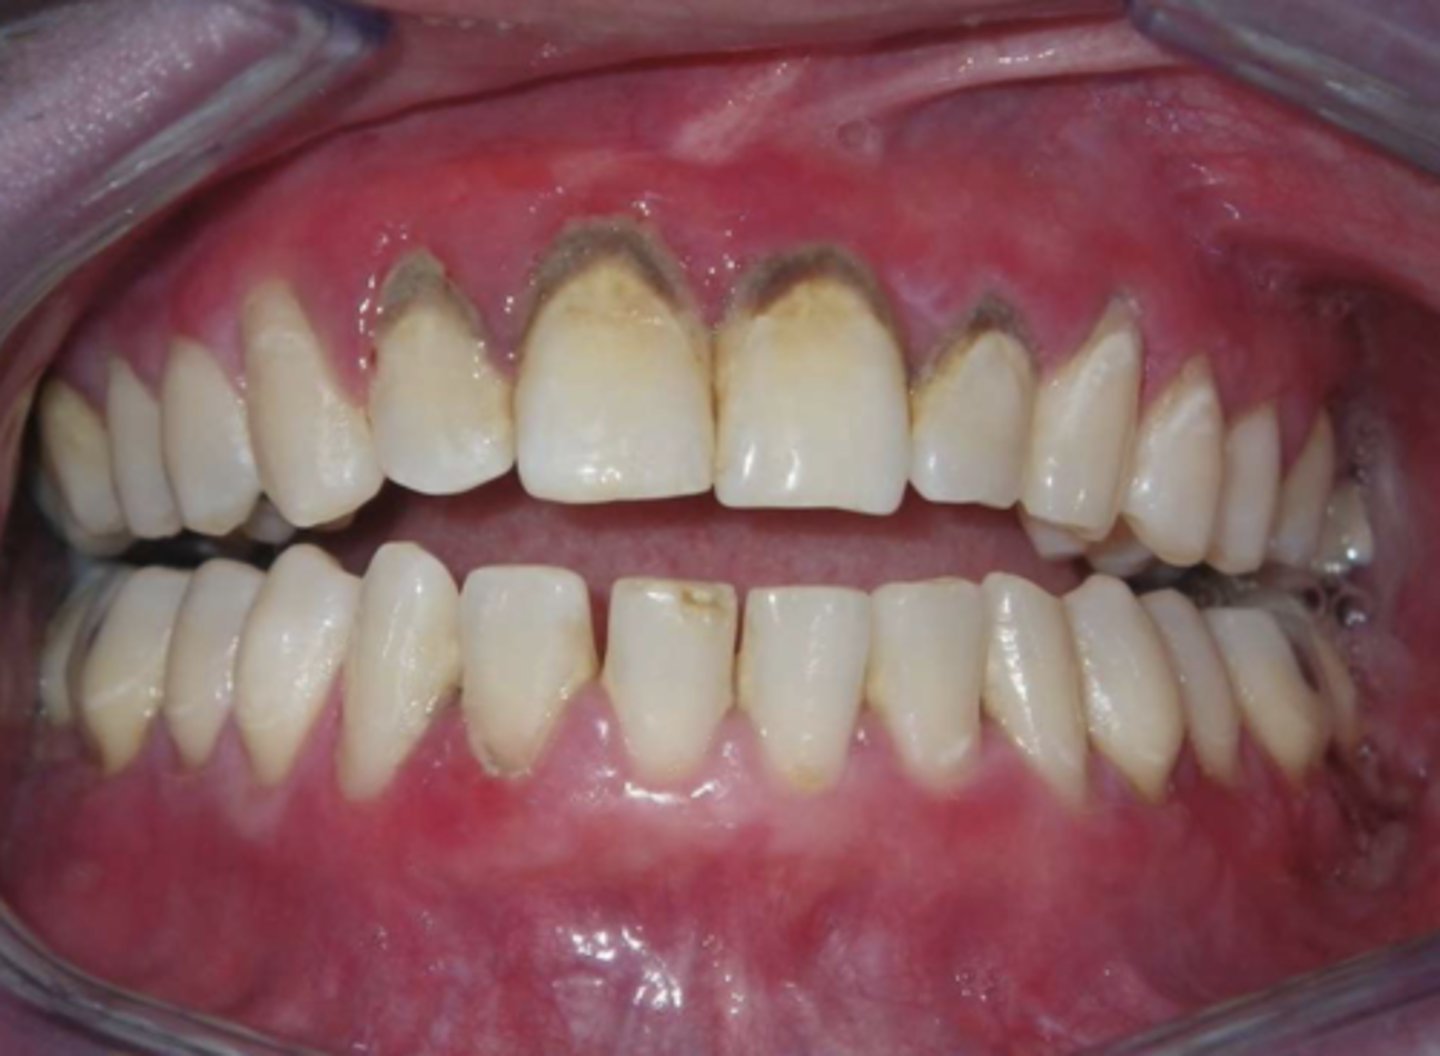

lichen planus (erosive/erythematous)

What type of lichen planus?

- Often symptomatic

- Striae at periphery of erythema

- May cause desquamative gingivitis

- Must be distinguished from mucous membrane pemphigoid or pemphigus

lichen planus (ulcerative)

- Least common form

- Usually symptomatic

- Ulcers w/ striae + erythema

lichen planus (ulcerative and some reticular and erythematous seen)

What condition?